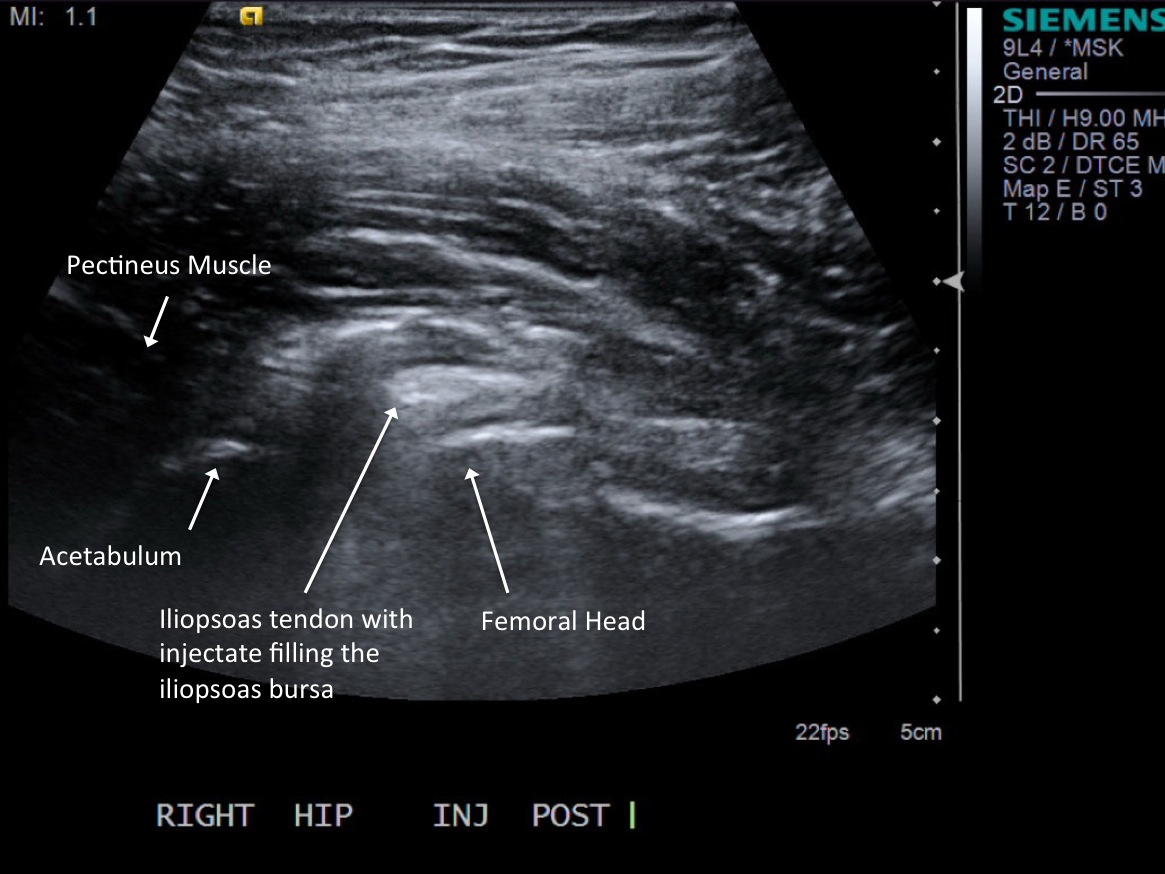

10. Test inject to see if easy flow with 1% lidocaine. If no resistance and see distention of the tendon sheath, exchange for 5cc syringe with injectable steroid and ropivacaine.

12. Scan joint to demonstrate distention. Can try to flex hip to see if fluid distended.

• descriptiondescription